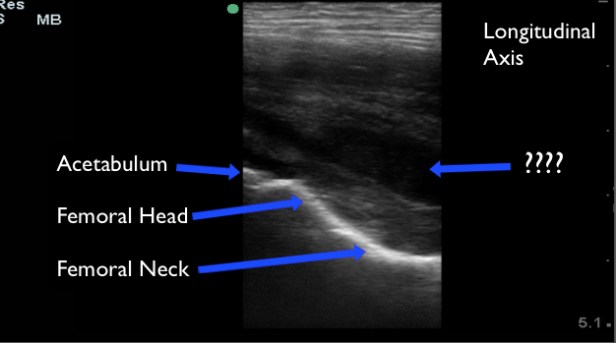

Upon our arrival to the hospital we performed a musculoskeletal POCUS of the bilateral hips. POCUS of the hip joint is best accomplished with the high frequency or linear probe in the pediatric patient, but low frequency probes may be used if the linear probe is unavailable. To evaluate the hip for an effusion with POCUS begin just medial to the ASIS, in a slightly oblique-sagittal plane. This will give you a longitudinal view of the hip joint. Identify the femoral head and acetabulum, followed by the femoral neck inferiorly. Hip effusions typically appear as an anechoic collection at the femoral head that extends to the femoral neck. You may also visualize effusions from the lateral position of the patient.

A collection that is not acute may not appear purely anechoic. However, there ought to be asymmetry when compared to the contralateral hip.